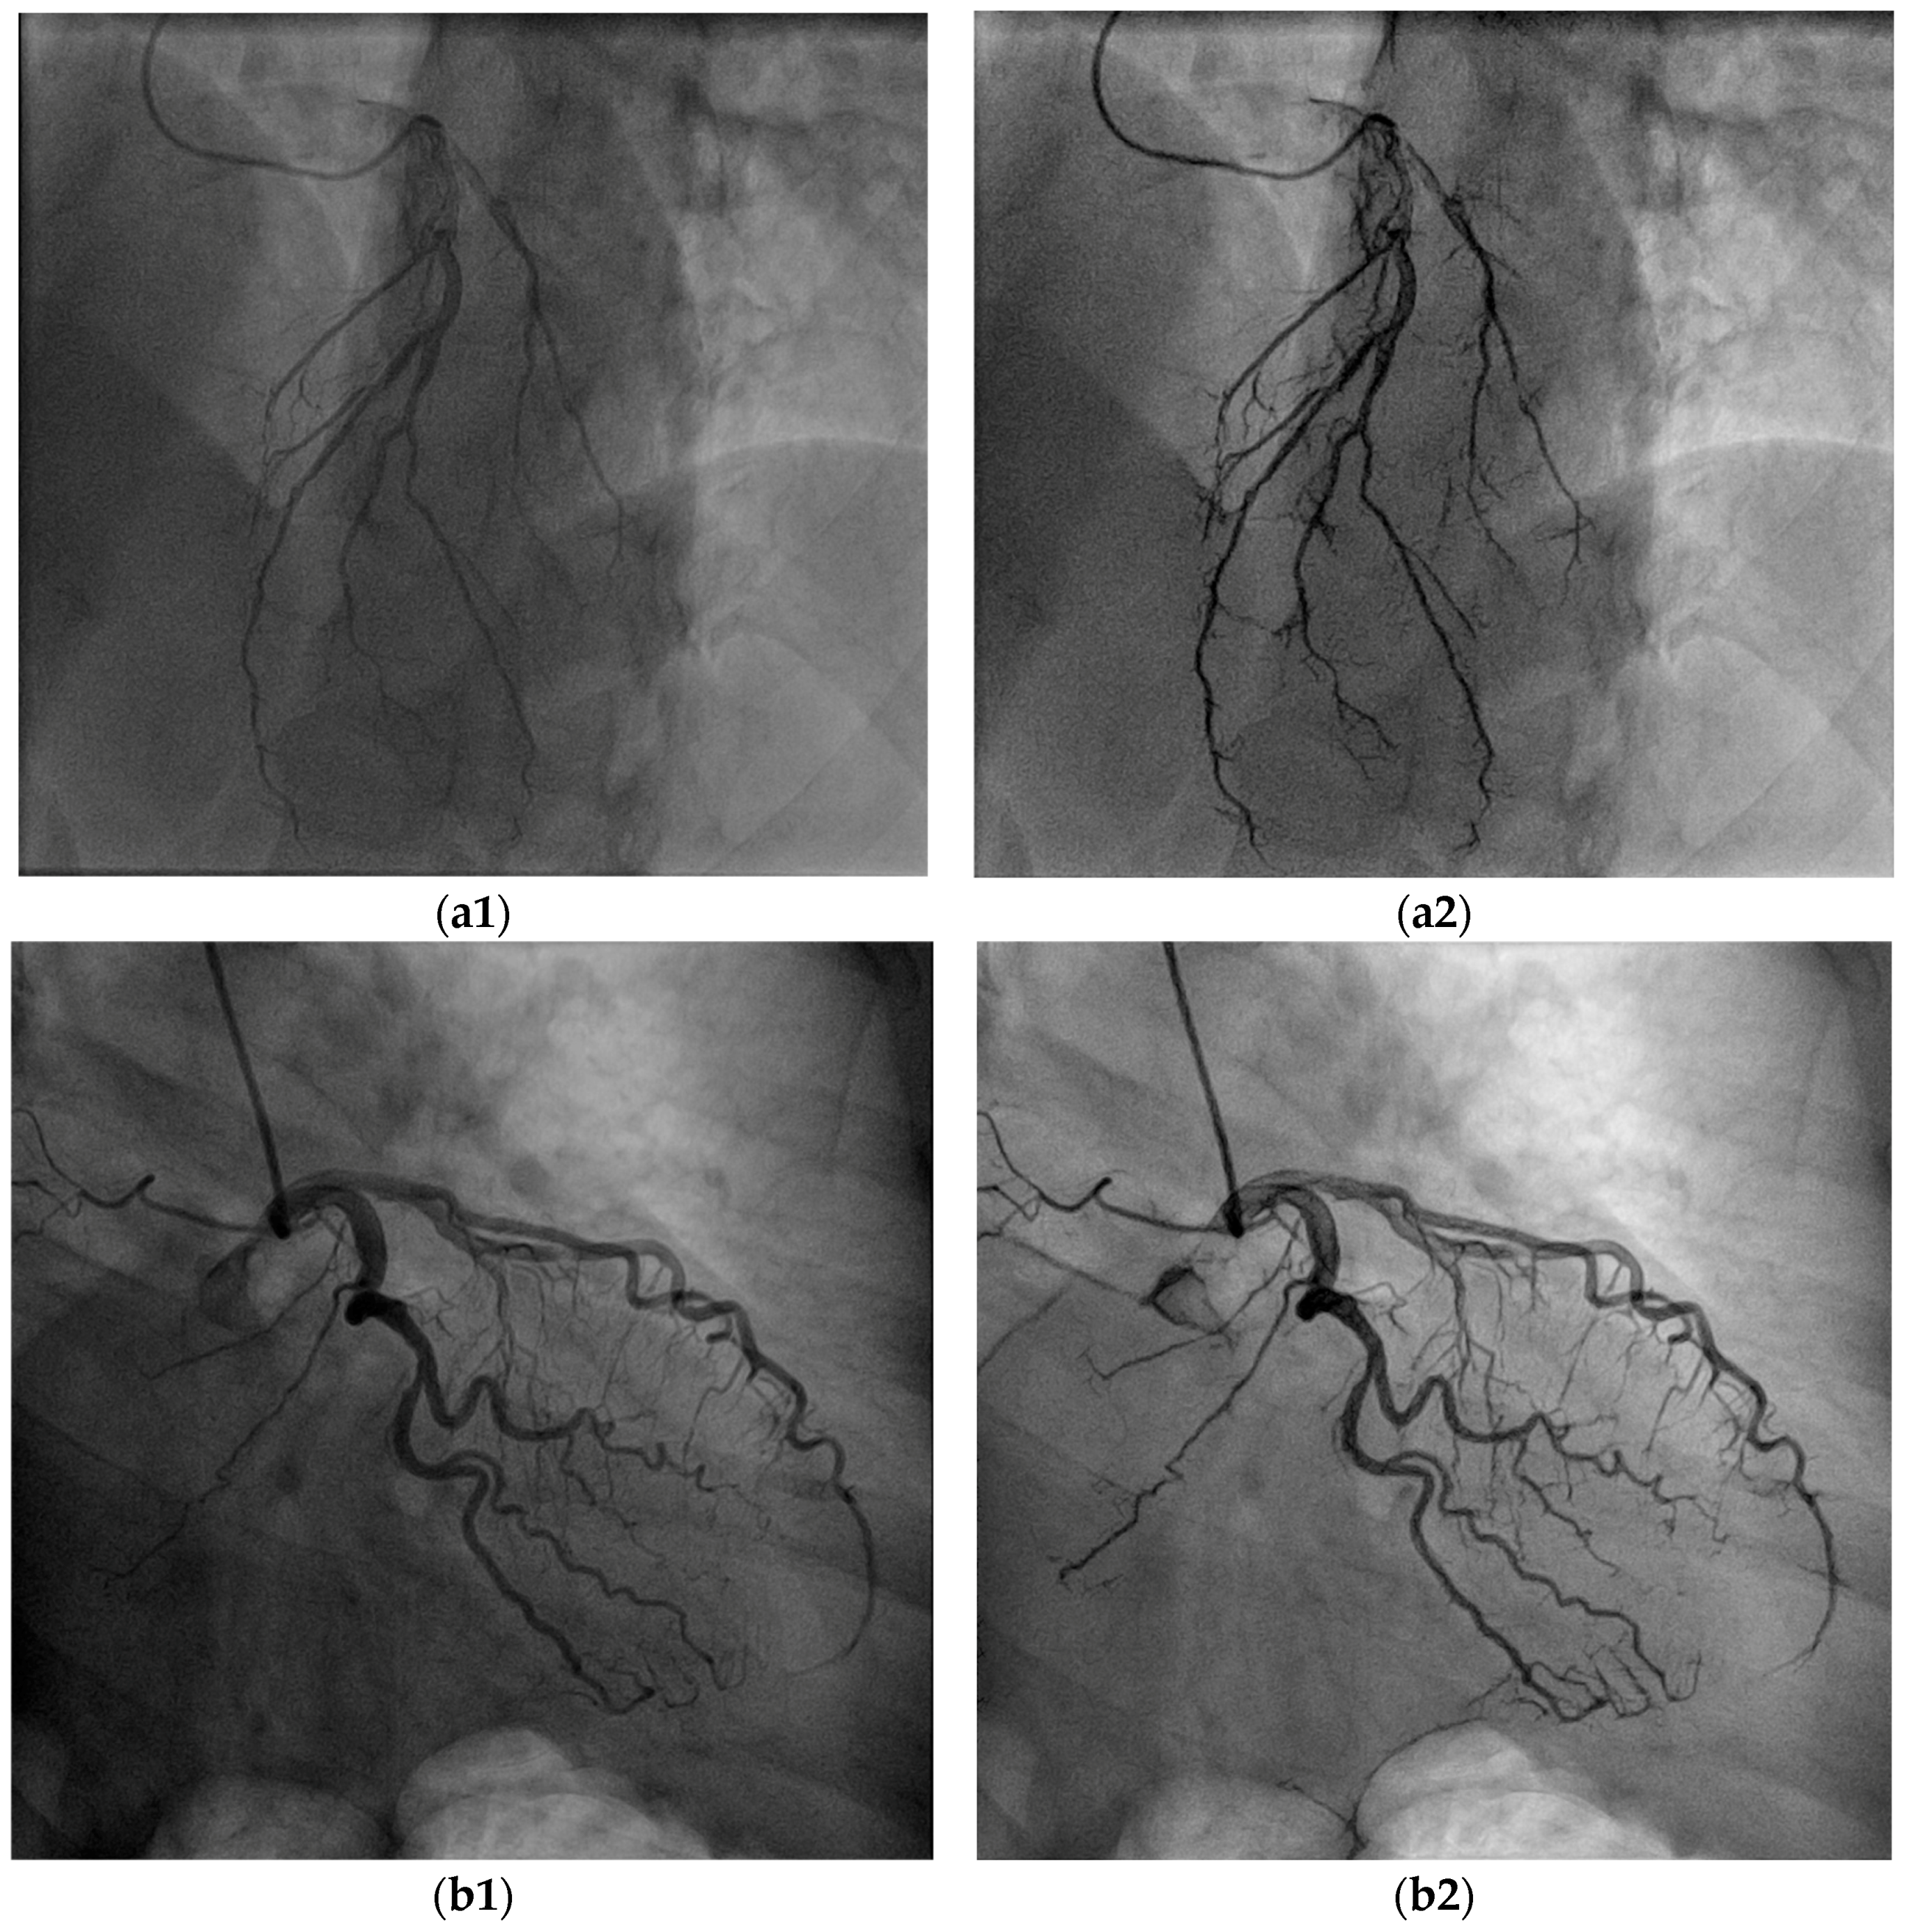

5.1. Overall Visibility Enhancement

5.2. Blood Vessel Interiors

5.3. Small Blood Vessels

5.4. Low-Contrast Agent, Low-Radiation, and No Contrast Agent